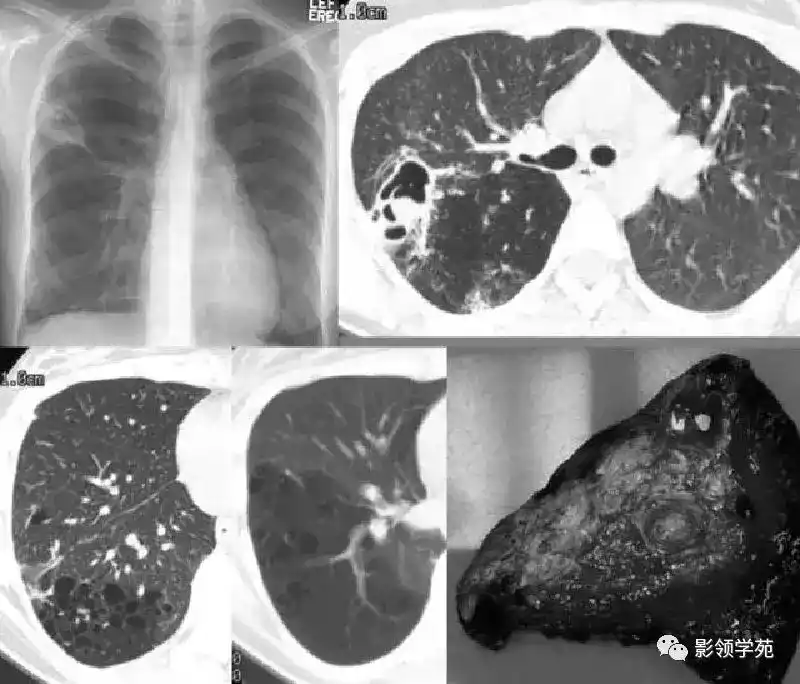

肺空洞是一种常见的疾病,它在肺部形成了一个孔洞。这个孔洞通常由于感染引起的肺组织坏死而形成。最常见的原因是结核菌感染,但也可能与其他细菌、真菌或寄生虫感染有关。当感染侵袭肺部时,免疫系统会试图清除感染,但有时会导致肺组织死亡,并形成空洞。

肺空洞的症状各异,包括持续咳嗽、咳出血痰、胸痛以及呼吸困难。然而,有些人可能没有任何明显的症状。要确诊肺空洞,医生通常会进行一系列检查,包括胸部X射线、CT扫描和支气管镜检查。这些检查可以帮助医生确定肺部是否存在空洞,并排除其他可能的疾病。